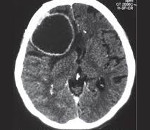

• Томографические исследования. Позволяют выявить внутримозговое образование с тонкими стенками, определить его локализацию и объем. КТ головного мозга более информативно в отношении кальциноза капсулы, МРТ головного мозга лучше визуализирует стенки кисты.